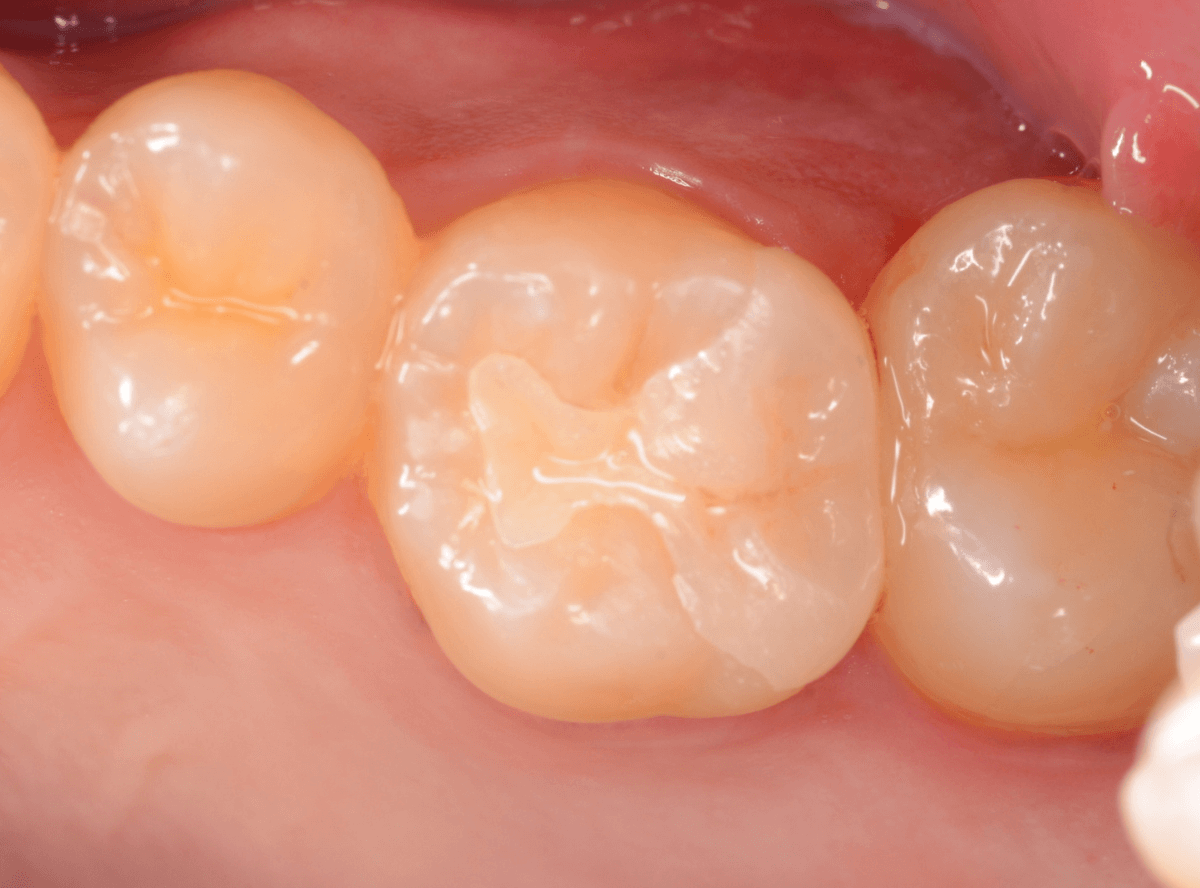

Case.1 奥歯のスキマが大きな虫歯!

他の歯の治療目的で来院された患者さんです。

全体検査の際、ちょっとこの歯、アヤシイなと思いましたが、確証はありませんでした。

(この写真で改めて見ると、かなりアヤシイと思いました)

レントゲン写真で確認すると、かなり大きな虫歯でした。

後日、改めて時間をお取りして、麻酔をかけて治療を開始です。

歯の表面を少し削ると、ボロッと虫歯が出てきました(>_<)

歯と歯の間の虫歯は、大抵は両方の歯に広がっている事がほとんどです。

今回のケースも、隣の歯まで、虫歯は広がっています。

最終的には、かなり神経に近いところまで虫歯が進んでいました。

もう少し遅かったら、危なかったと思います。

他の歯の治療で来院された事が、幸運でした。

しばらく経過観察した後、特に症状がありませんでしたので、隣の歯をレジンで治療後、ジルコニア・インレー(70,000円(税込み/2024年1月現在))で治療することにありました。

治療後の写真です。

特に症状もなく、審美性も高く治療することができました♪